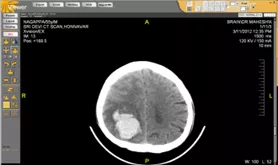

CT of the brain can be done with or without contrast, but it is not necessarily required. CT scanning of the brain is done in cases of bleeding, brain injury and skull fracture as well as for cerebral aneurysms. Even in cases of enlarged brain in patients with hydrocephalus this unique imaging technology is very helpful. The other medical symptoms for which this scan is called for could be anything from a headache, weekness, seizure, confusion, etc.